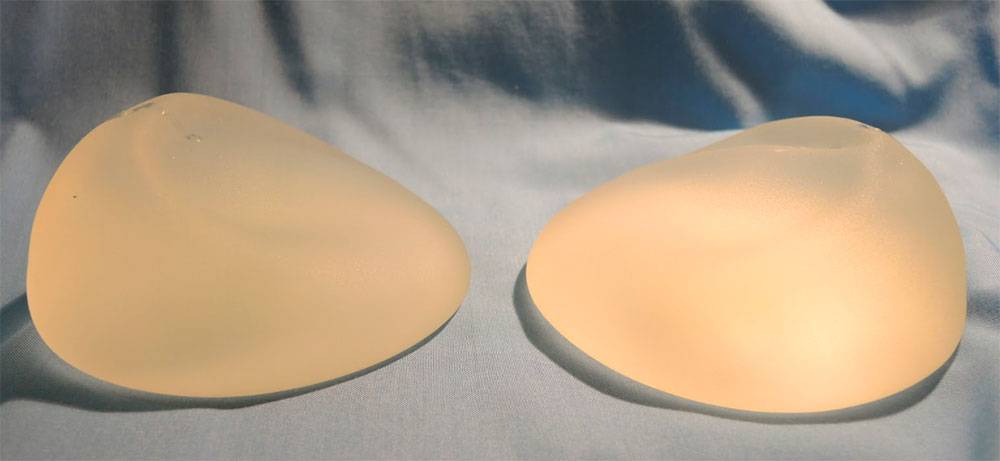

Анатомические импланты Eurosilicone

Раздел: Визуальный дайджест